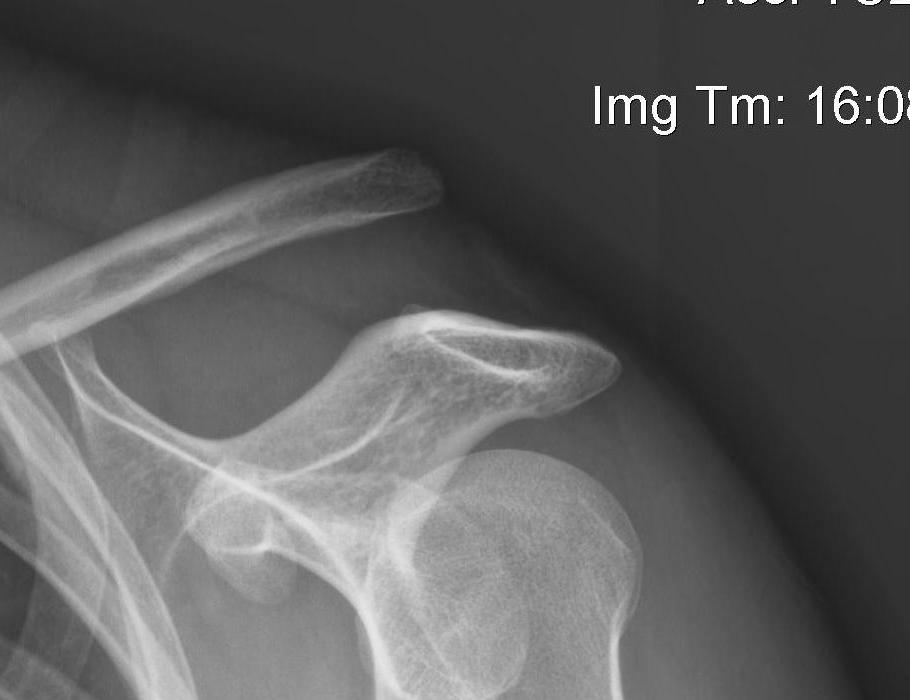

Subcoracoid dislocation case report